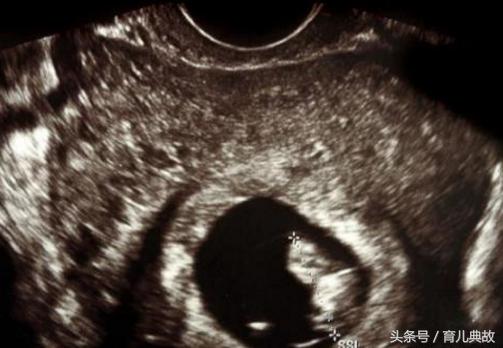

在三个月去医院建卡,B超检查完后说怀的是双胞胎,那一刻就好像中了彩票,三番四次的问医生是不是真的,在听到医生肯定的话,开心的就像中了五百多万。

单胎变双胎的惊喜真的太不可思议了,何其幸运能一次迎来两个宝宝。医生表示,若早期孕囊B超单上出现"宝宝偏大一周/两周"的字样以及HCG值偏高的时候是有可能从单胎变双胎的,在现实生活中也有过不少案例。

当初之所以瞒着有可能是双胞胎,主要是怕孕妇空欢喜一场,现在在看到B超中显示的两个胎芽胎心,就确定了双胎的事实。